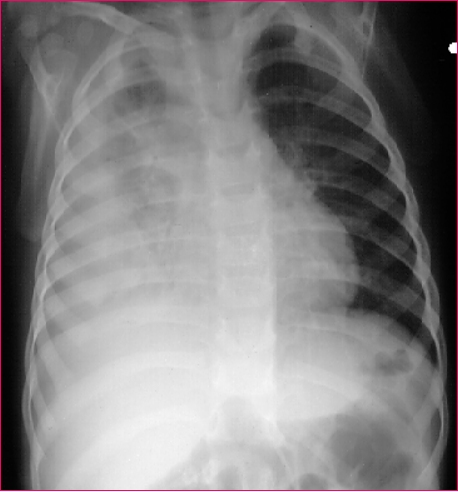

肺不张

3月龄女婴患肺炎后情况:

胸部 X 线检查所见:右下叶

肺不张的 锲形阴影(箭头)

(正位)右上叶肺不张